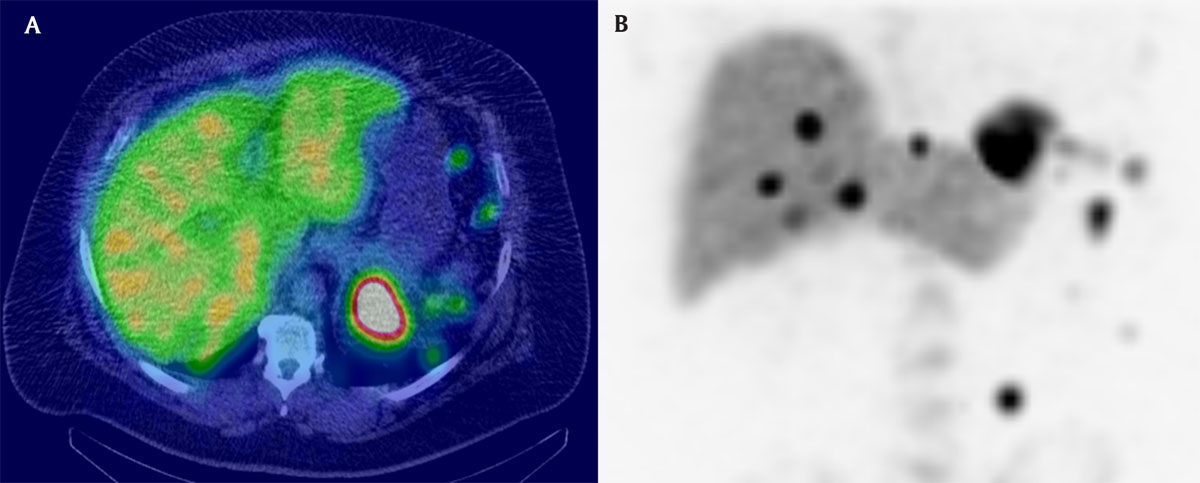

The additional abdominal contrast-enhanced CT revealed multiple other nodules and homogeneous disseminated peritoneal masses (Figure 1B–C1). Splenosis nodules were suspected given the history of splenic trauma and the lack of cancer history. A Tc-99m-tagged heat-damaged red blood cells scintigraphy (Tc99m-DRBC) confirmed the diagnosis of peritoneal splenosis (Figure 2).

Fusion Tc99m-DRBC + CT axial slice (A) and coronal maximal intensity projection reconstruction of the scintigraphy (B) demonstrating uptake of these multiples nodular lesions.

Tc99m-DRBC is the best examination method to confirm the diagnosis of splenosis, as the ectopic splenic tissue absorbs most of the damaged red blood cells [1]. It is much more sensitive and more specific than Tc-99m-labeled sulfur colloid scintigraphy.